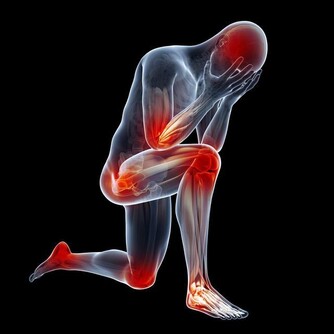

30歲開始,關節痠、痛、軟!

關節退化,是免不了的老化過程。

運動過度、關節受傷、過度肥胖等,都會使關節提早退化,

而膝關節、髖關節、脊椎等,是最容易退化的關節部位。

健康的關節要達到穩定且可大範圍的活動,

有賴於完整的骨頭、控制良好的肌肉、健全的神經系統、穩固的韌帶等條件配合,

只要任何一個環節出問題,關節就無法正常活動,

進而產生疼痛、活動不良、行動不穩定等問題。